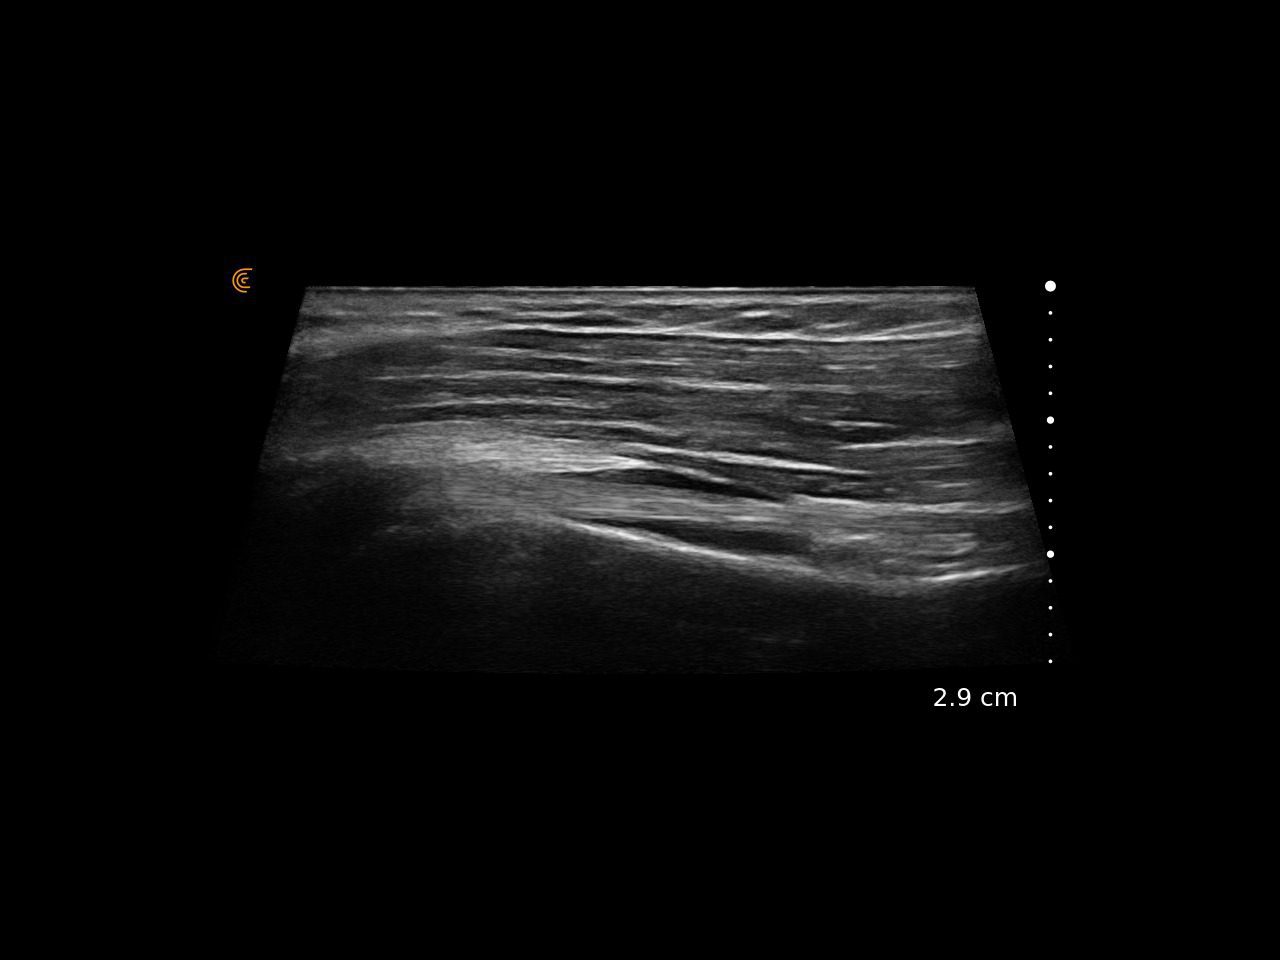

Specialized presets and high resolution provide fast, accurate imaging for athletes’ needs.

Use real-time imaging to assess injuries, monitor recovery, and tailor treatment plans—delivering better outcomes for every patient.